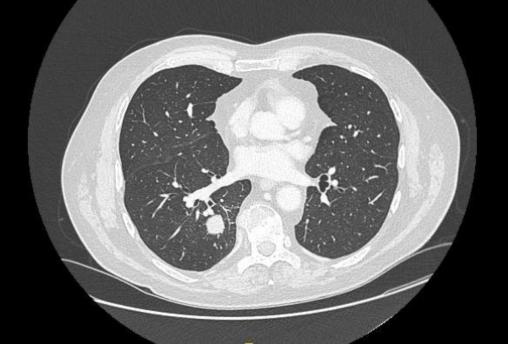

Institut Gustave Roussy Scanner thoracique de surveillance. Coupe de scanner thoracique en fenêtre parenchymateuse, un nodule du lobe inférieur droit d’allure solide et suspecte (contours spiculés).